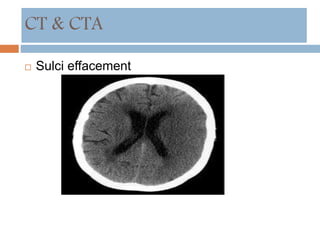

CT & CTA

 Sulci effacement